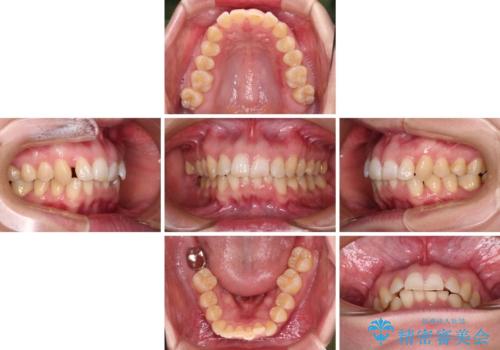

カリエール・ディスタライザーとインビザラインを用いた前歯の咬み合わせ改善

- 上顎前歯の前方に傾斜した咬み合わせを気にして来院された患者様です。

奥歯の咬み合わせを見ると、上顎が下顎に対して相対的に前方にありました。

深い咬み合わせを改善するためには、上顎臼歯を後方に移動させつつ、下顎の小臼歯を直立させる必要があります。

インビザライン単体で対応ることも検討できますが、達成する可能性が低いため、カリエールディスタライザーという補助装置を併用して、より確実性を上げることとしました。

奥歯の咬み合わせと深い咬み合わせを改善した後、インビザラインで歯列を整えることとしました。